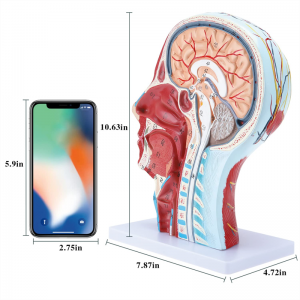

| Numele produsului | Craniu uman cu model neurovascular muscular |

| Material | PVC |

| Dimensiune | 21*12*27cm |

| Caracteristici | Modelul arată morfologia locală a laturilor interioare și exterioare ale secțiunii sagitale mediane a capului și a gâtului, precum și a structurilor vaselor de sânge și a nervilor și există 84 de părți care indică semne în total. |

【1: 1 LIFESIZE】 Secțiune mediană din 1: 1 Modelul mușchiului vascular neural superficial al capului mare și al gâtului natural (partea dreaptă). Manopera fină. Oferind o gamă completă de caracteristici anatomice.

【Model de anatomie a creierului de înaltă calitate, realizat din material din PVC ecologic non-toxic, ușor de curățat. Modelele de anatomie sunt pictate manual și asamblate cu cea mai mare atenție la detalii.

【Model de mușchi neurovascular superficial】 extrem de detaliat, numere marcate, detașabile, adânciți înțelegerea mușchilor superficiali, vaselor, nervilor și structurilor interne ale capului și gâtului. Red-Artery, vene albastru, galben-port.

【Caracteristici】 arată mușchii superficiali ai feței expuse; vasele de sânge superficiale și nervii feței & scalp; structurile interioare ale glandei parotide și ale tractului respirator superior; Structura de secțiune sagitală a coloanei vertebrale cervicale.

【Aplicație】 Acest model este prima alegere pentru Oficiul Doctorului, Școala, Hosipital și Clincs. Într -adevăr un mare ajutor didactic pentru cursuri de anatomie și fiziologie, demonstrație, instrument de comunicare pentru medici și pacienți.

Acest model arată detalii despre gâtul dreptului drept și secțiunea sagitală mijlocie a omului. inclusiv superficialul

mușchii feței expuse; vasele de sânge superficiale și nervii feței și ale scalpului; Structurile interioare

a glandei parotide și a tractului respirator superior; Structura de secțiune sagitală a coloanei vertebrale cervicale.

Modelul a arătat morfologia locală a secțiunilor sagitale mediale și laterale ale capului și gâtului și ale structurilor sale vasculare și nervoase, cu un total de 100 de indicatori de sit.

Acest model este un model natural de mușchi neurovascular superficial al capului și gâtului, 1 componentă, care arată detaliile capului drept și gâtului drept și secțiunea sagitală mediană, inclusiv mușchii superficiali expuși ai feței, vasele superficiale ale feței și scalpului, nervii și structura medială a glandei parotide și a tractului respirator superior și a structurii secțiunii sagitale a coloanei vertebrale cervicale